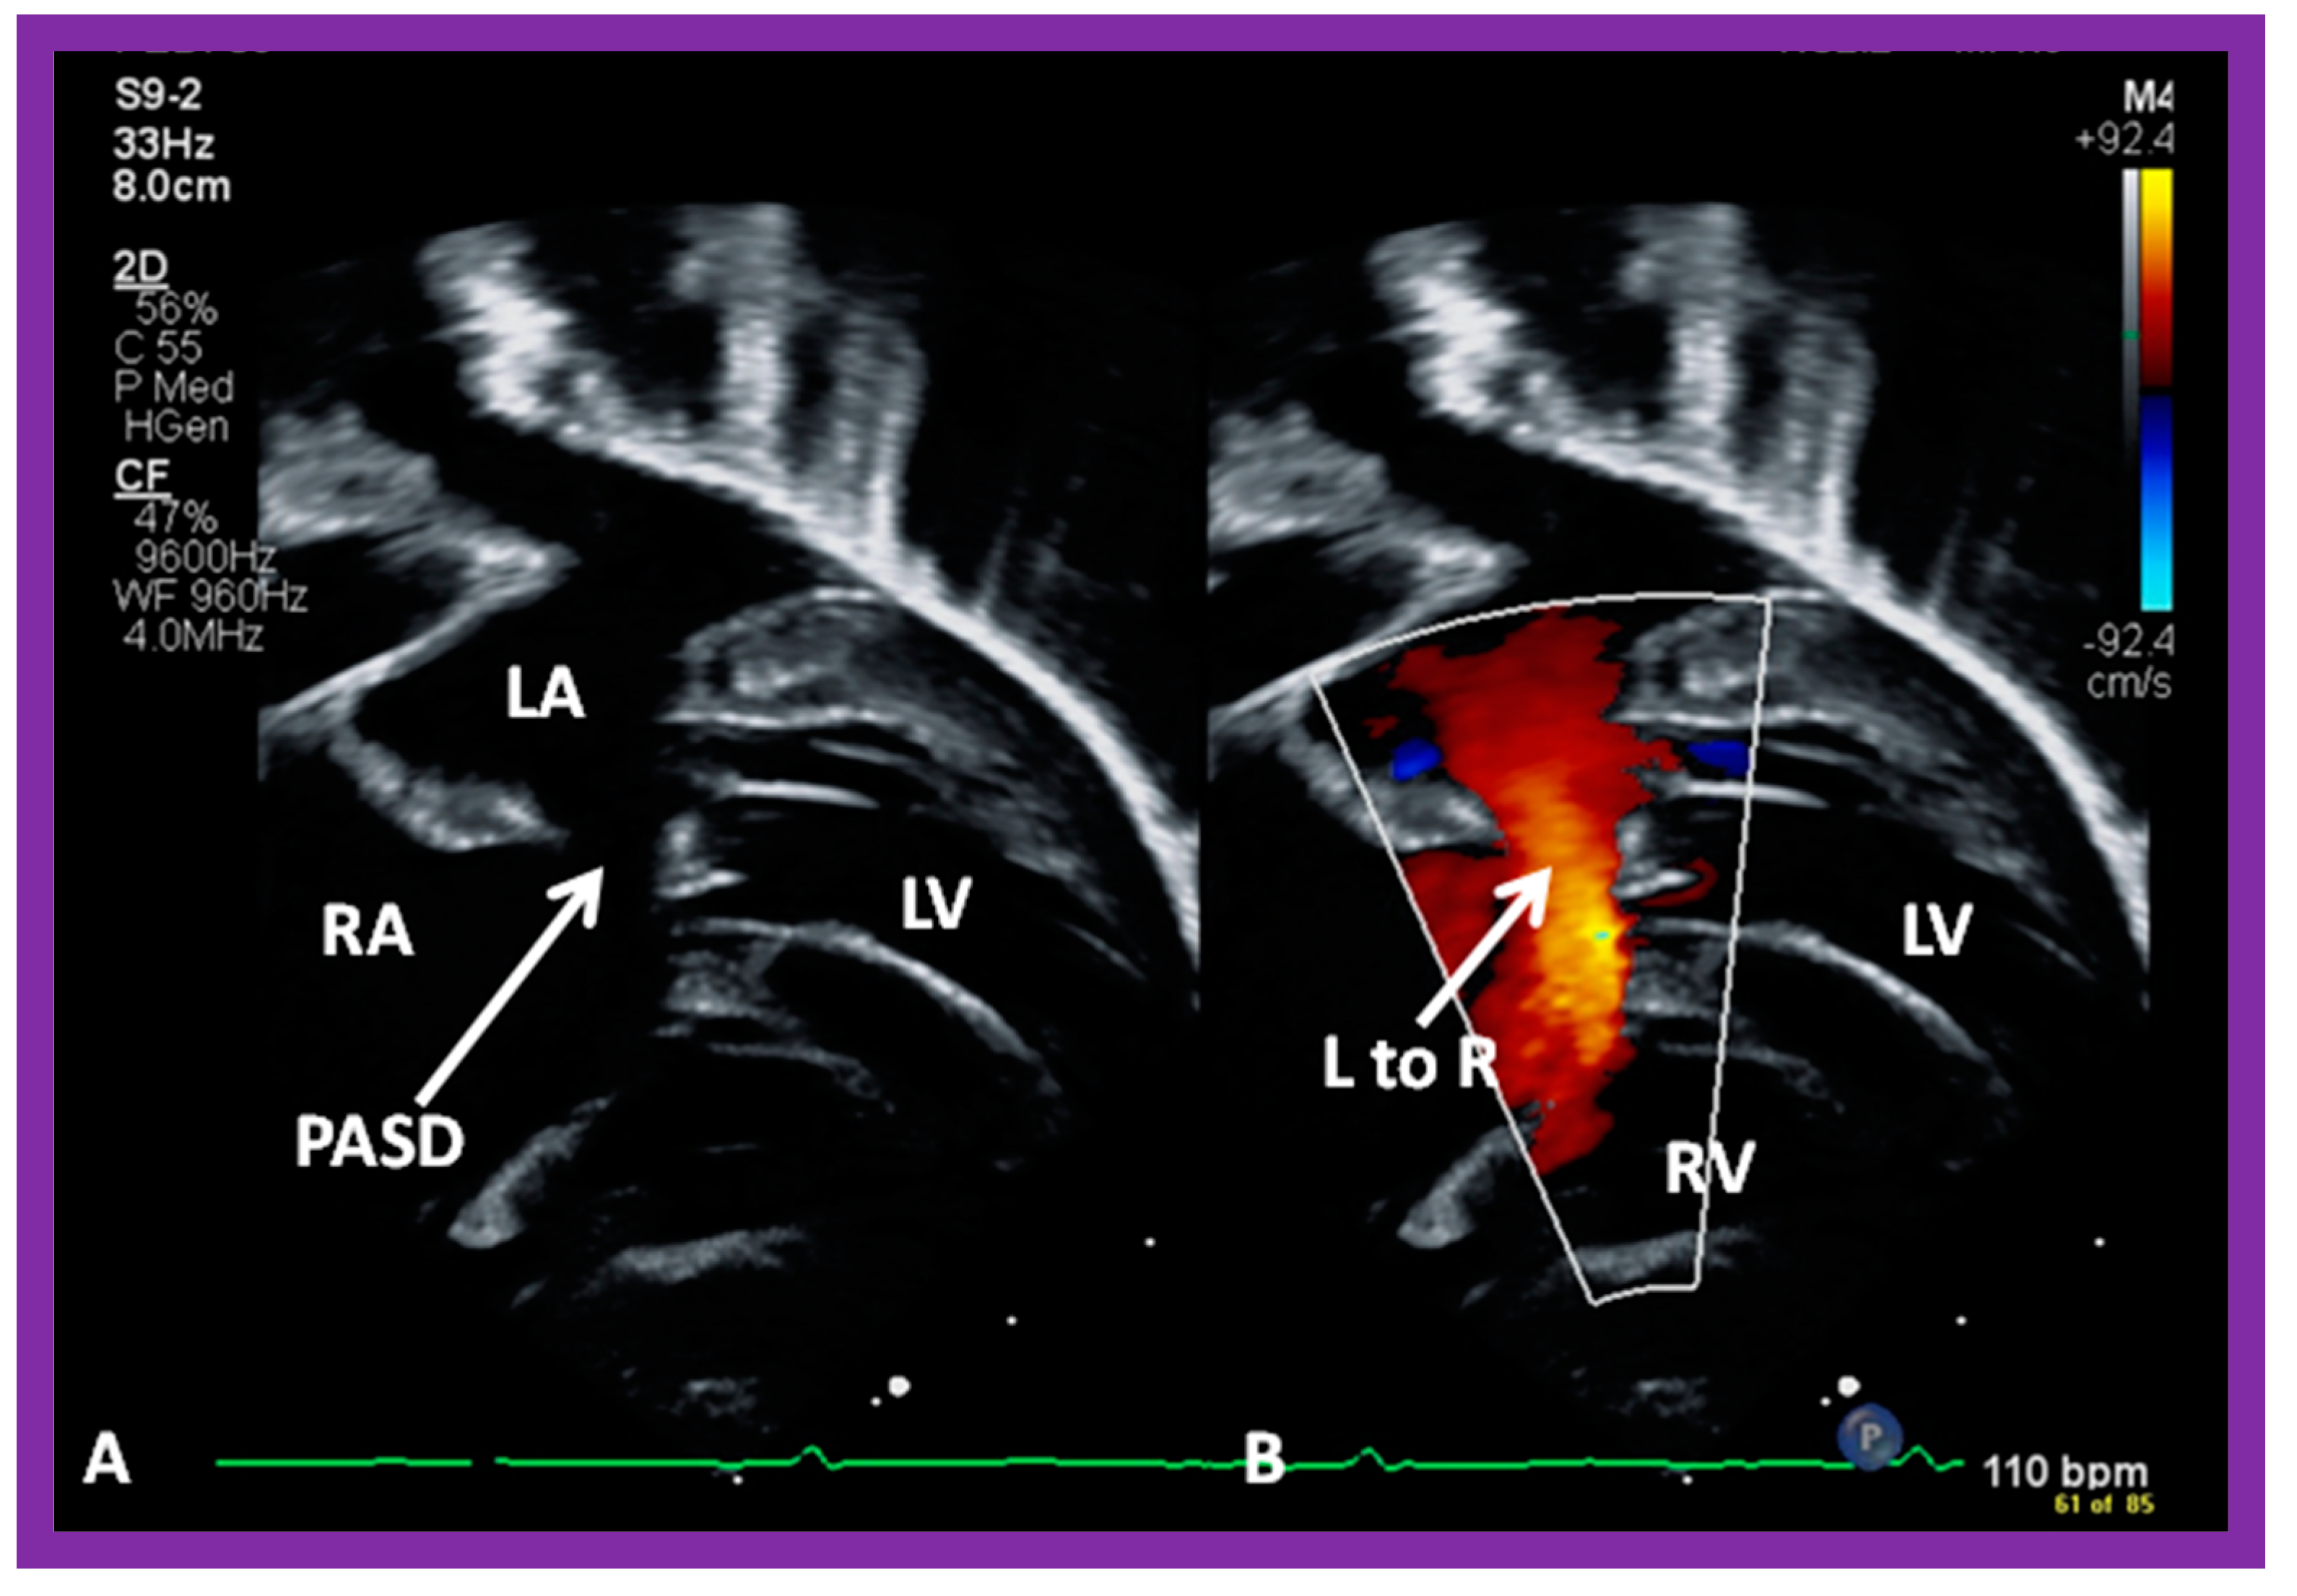

2. Diagnosis